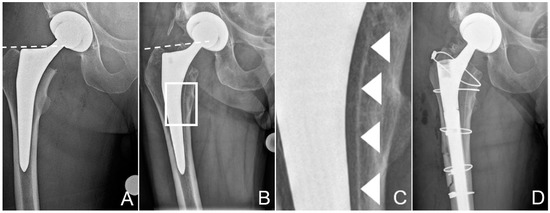

2.1. Case Description